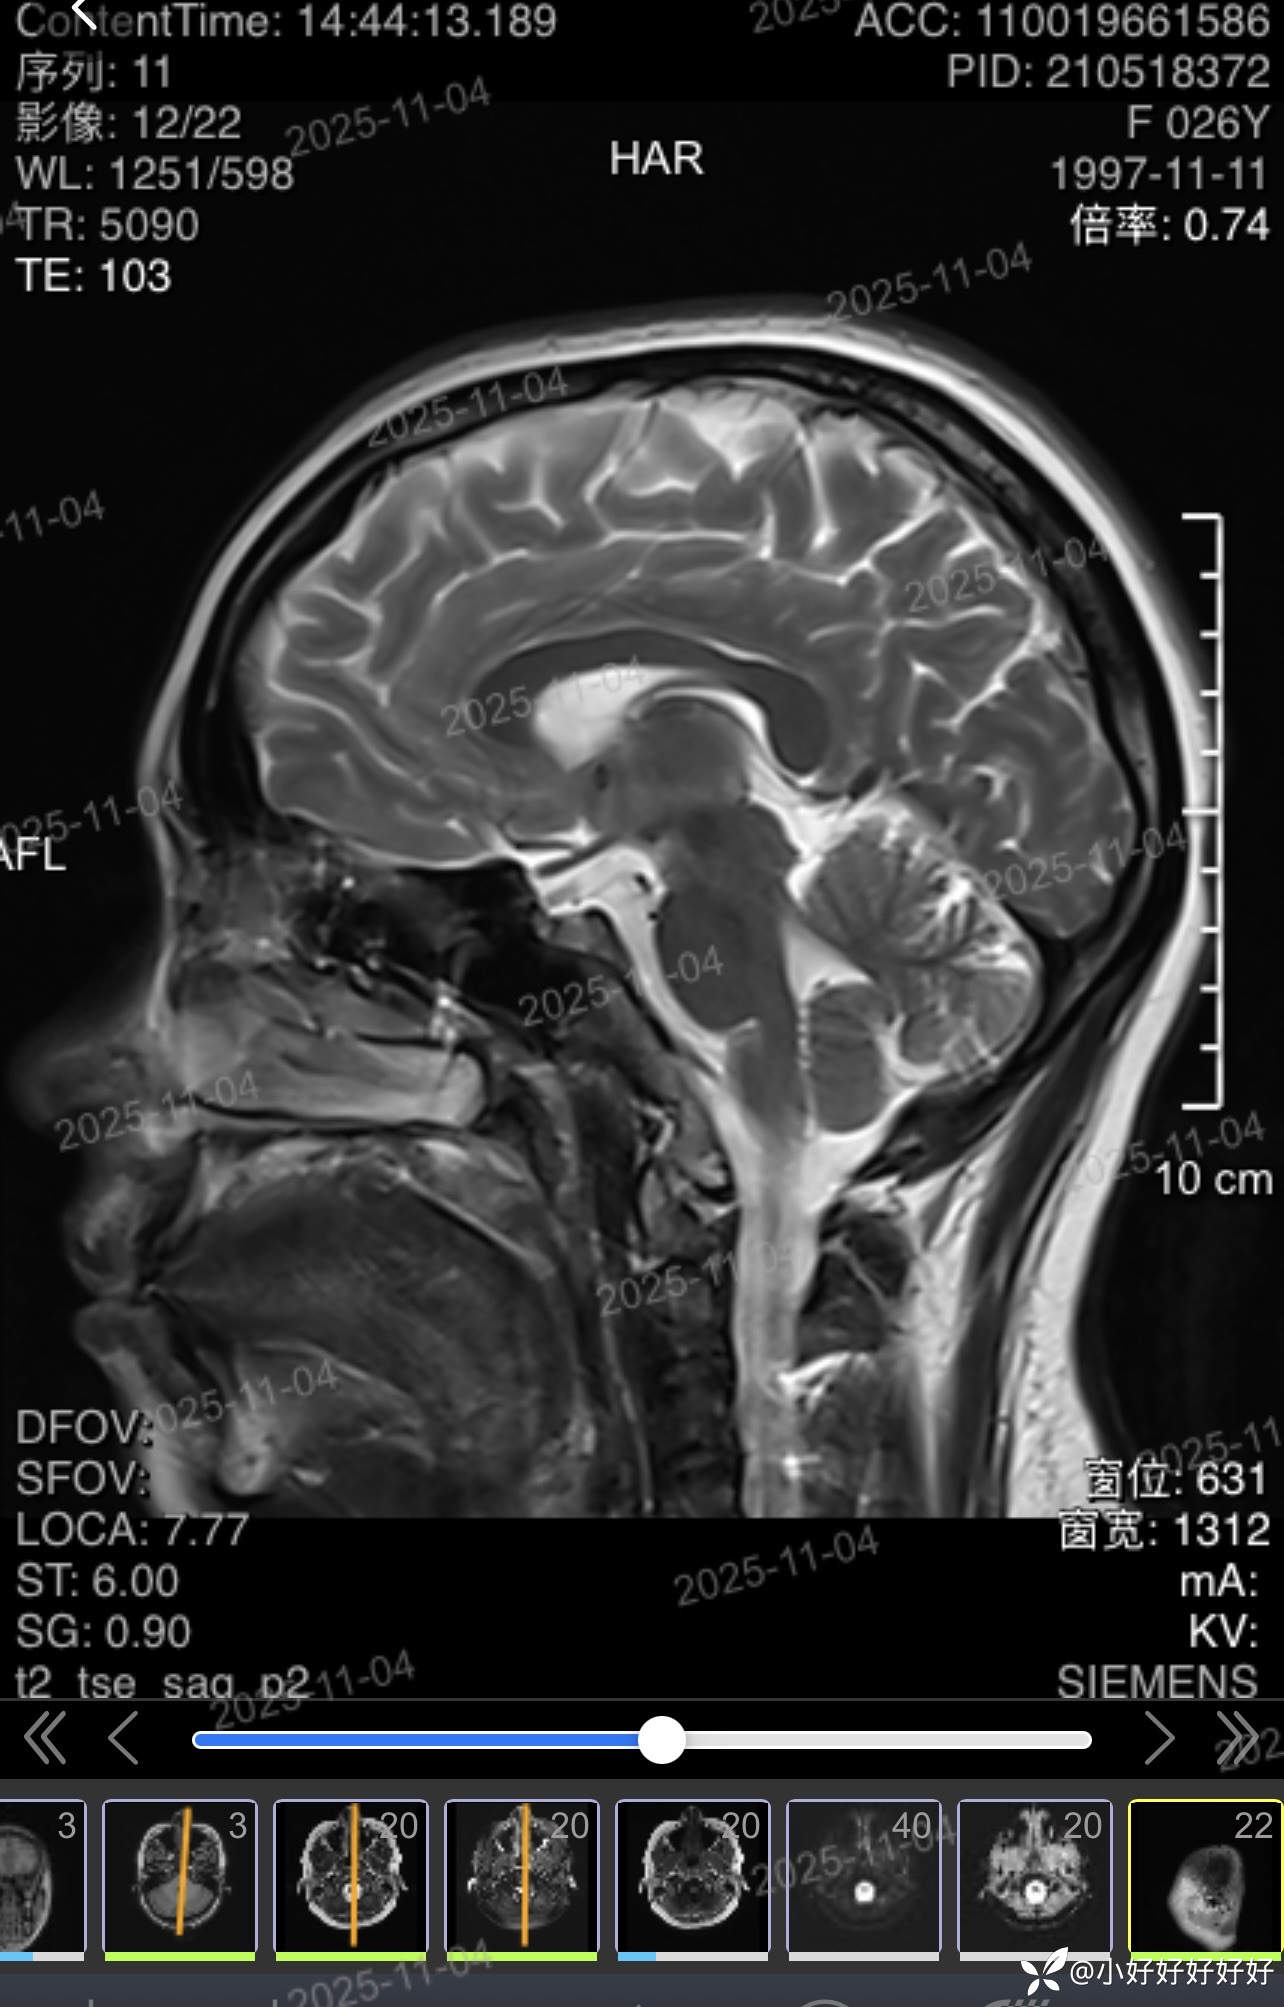

图1.2是病人现在的

图3是病人半年前的

这样是否异常?